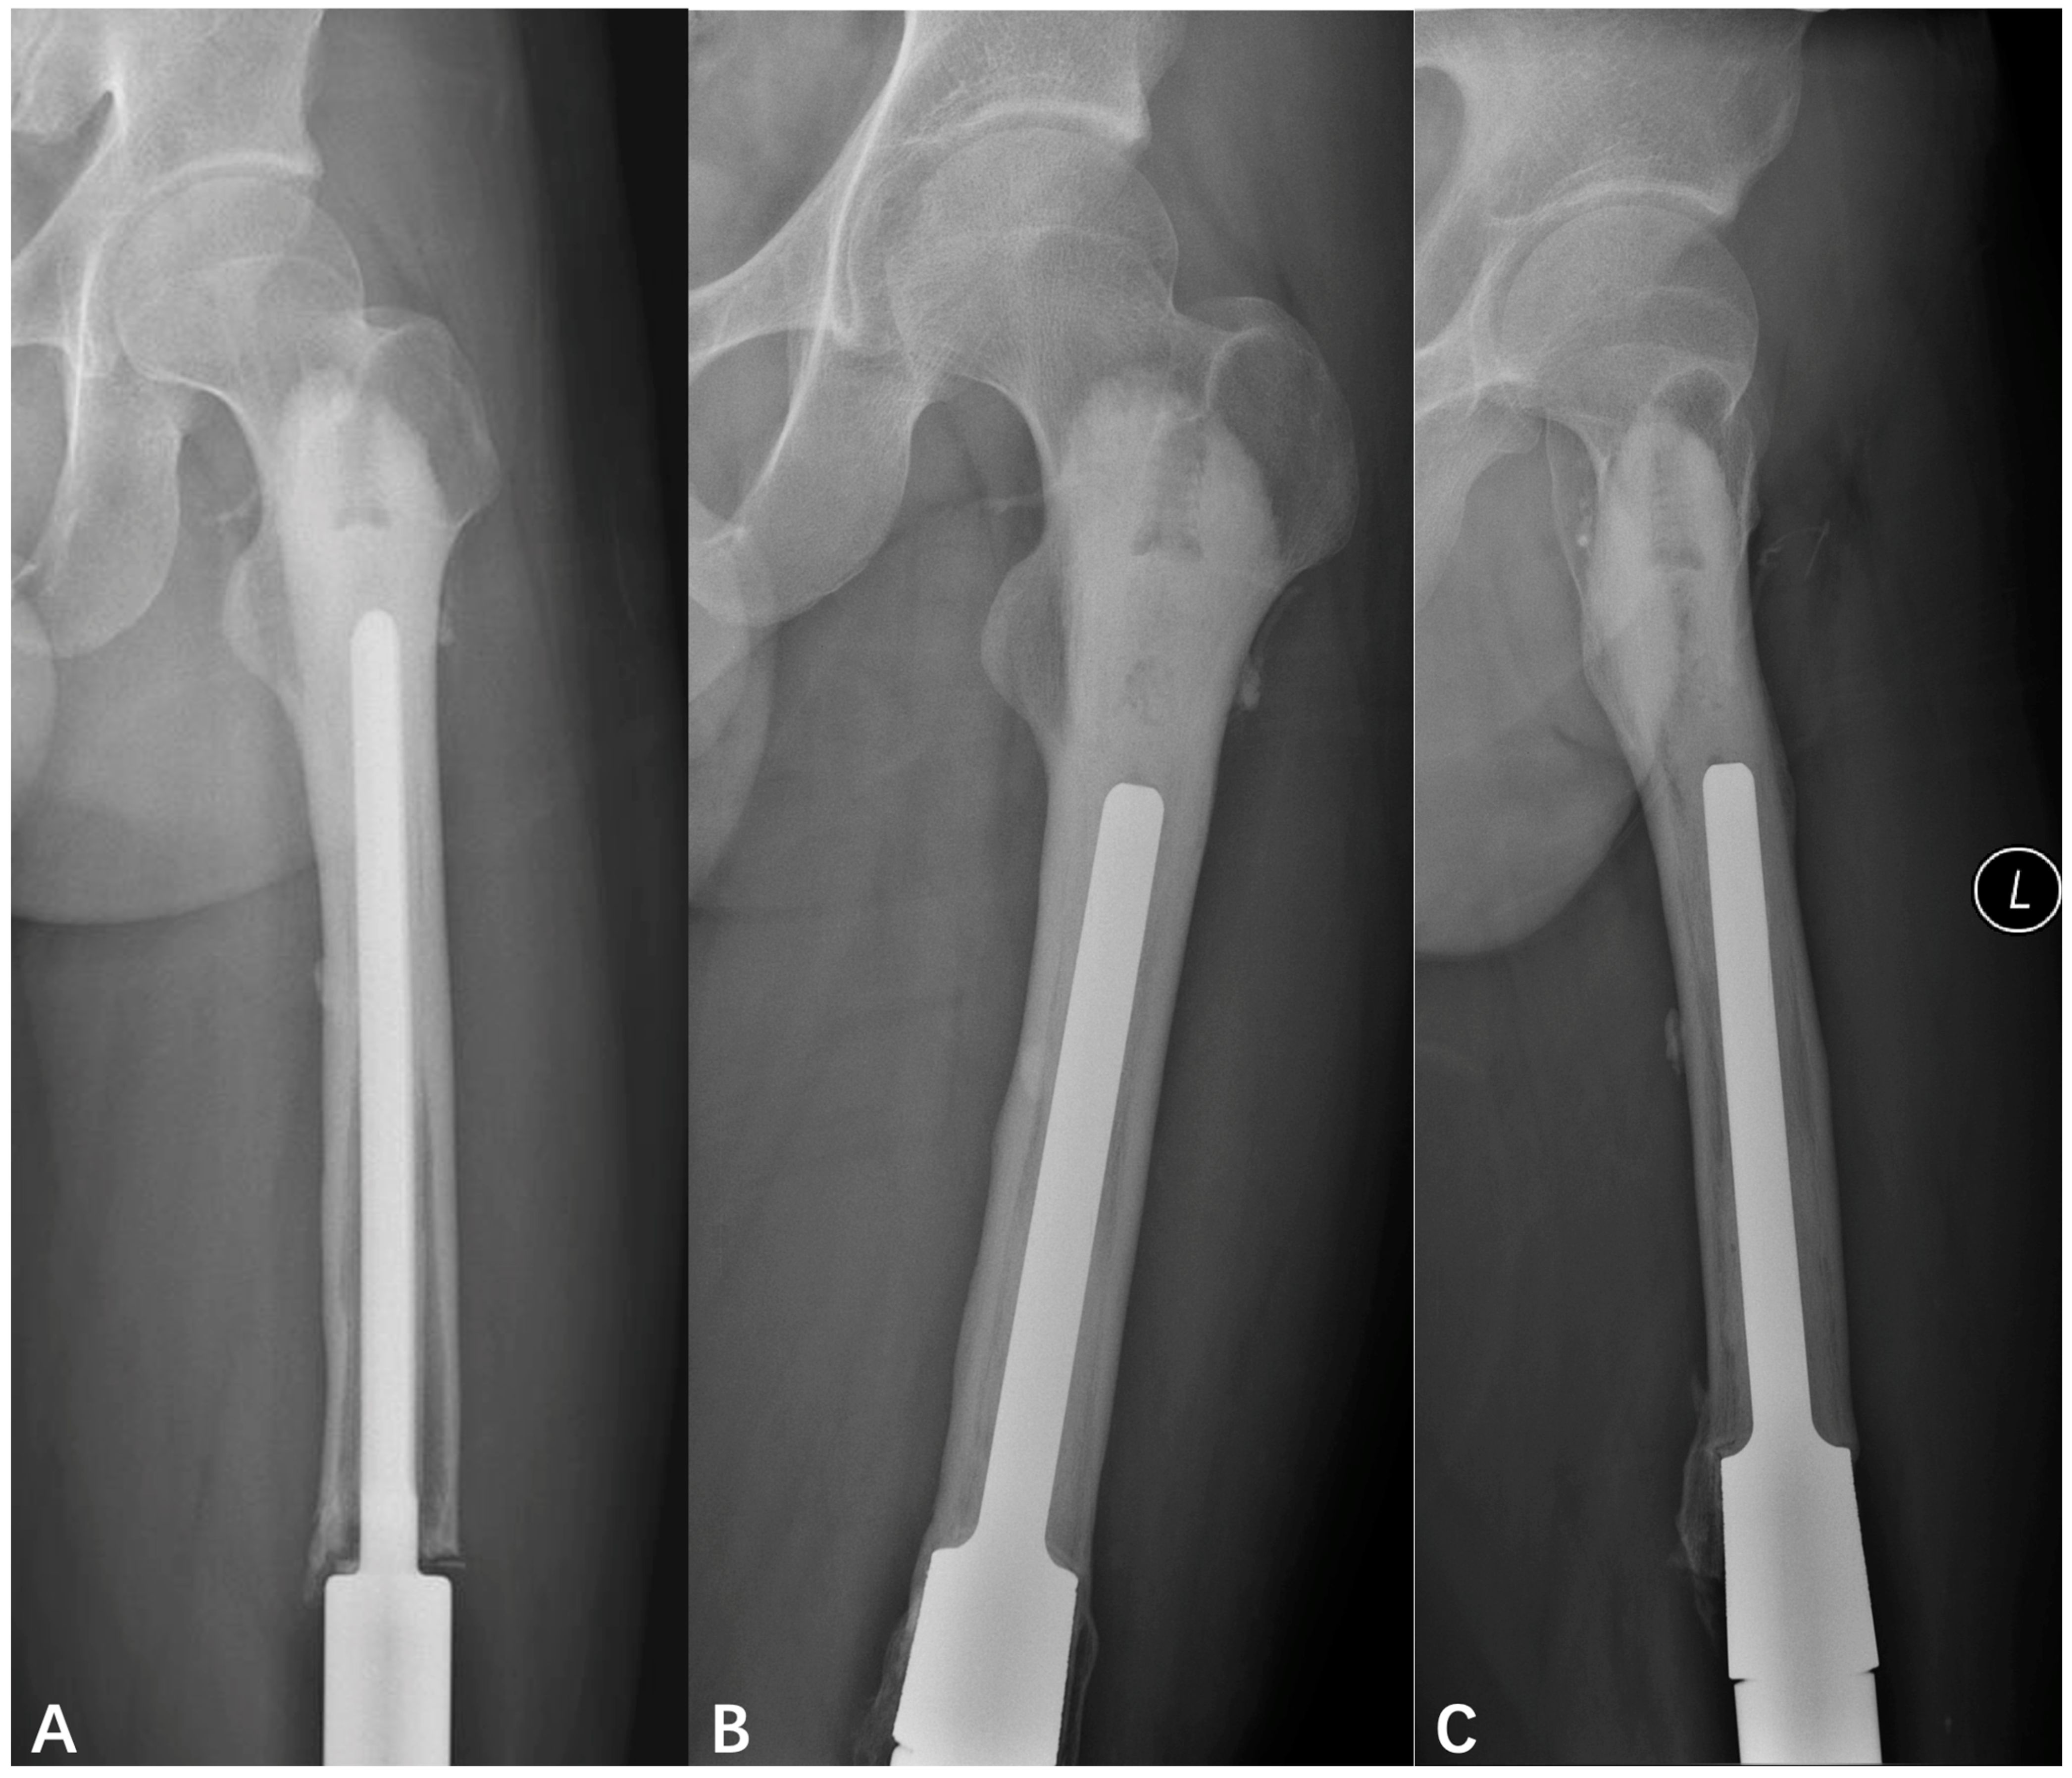

GMRS Oncological Prosthesis with a Porous Coating Collar: A Good Option for Revision of Aseptic Loosening in the Lower Extremity

3.2. Evaluation of Aseptic Loosening